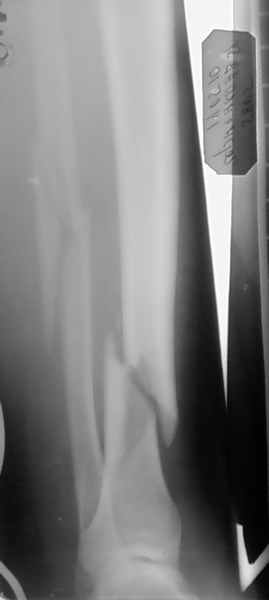

Ув. колеги, в представленном на снимках случае, возможно выполнить проведение блокируемого стержня без аппарата ЭОП ?

Заранее благодарен за отзывы и коментарии !!!!